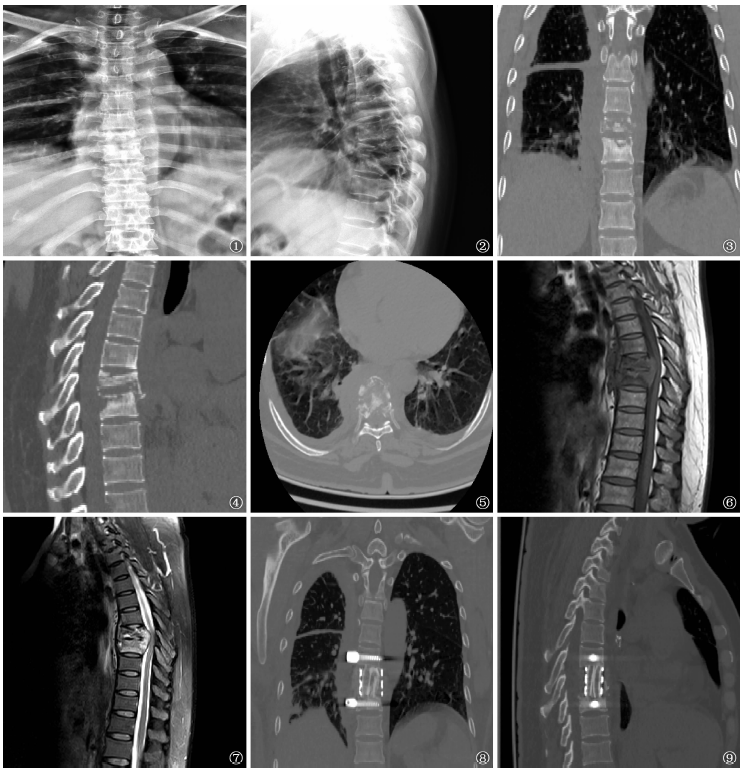

图1~9 患者,男,48岁,胸7、8椎体结核,术前化疗时间为6d。图1~2 为X线摄片,显示胸7、8椎体骨质破坏,椎间隙明显狭窄。图3~4为脊柱CT扫描二维重建,显示胸7、8椎体骨质破坏,可见死骨,椎旁脓肿,椎间隙明显狭窄。图5 为CT断层扫描,显示椎体虫蚀样骨质破坏,可见死骨及椎旁脓肿。图6~7为MRI,显示T1WI胸7、8椎体低信号,T2WI胸7、8椎体高信号,相应椎管内脓肿形成,压迫脊髓。图8~9 为脊柱CT扫描二维重建,显示胸7、8椎体间钛笼植骨块融合良好,内固定位置佳